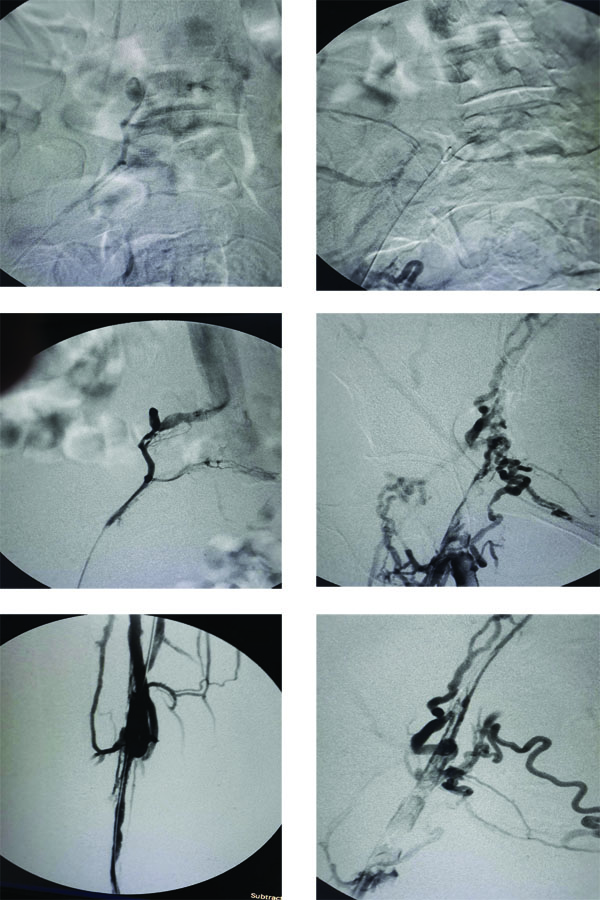

Medical achievement